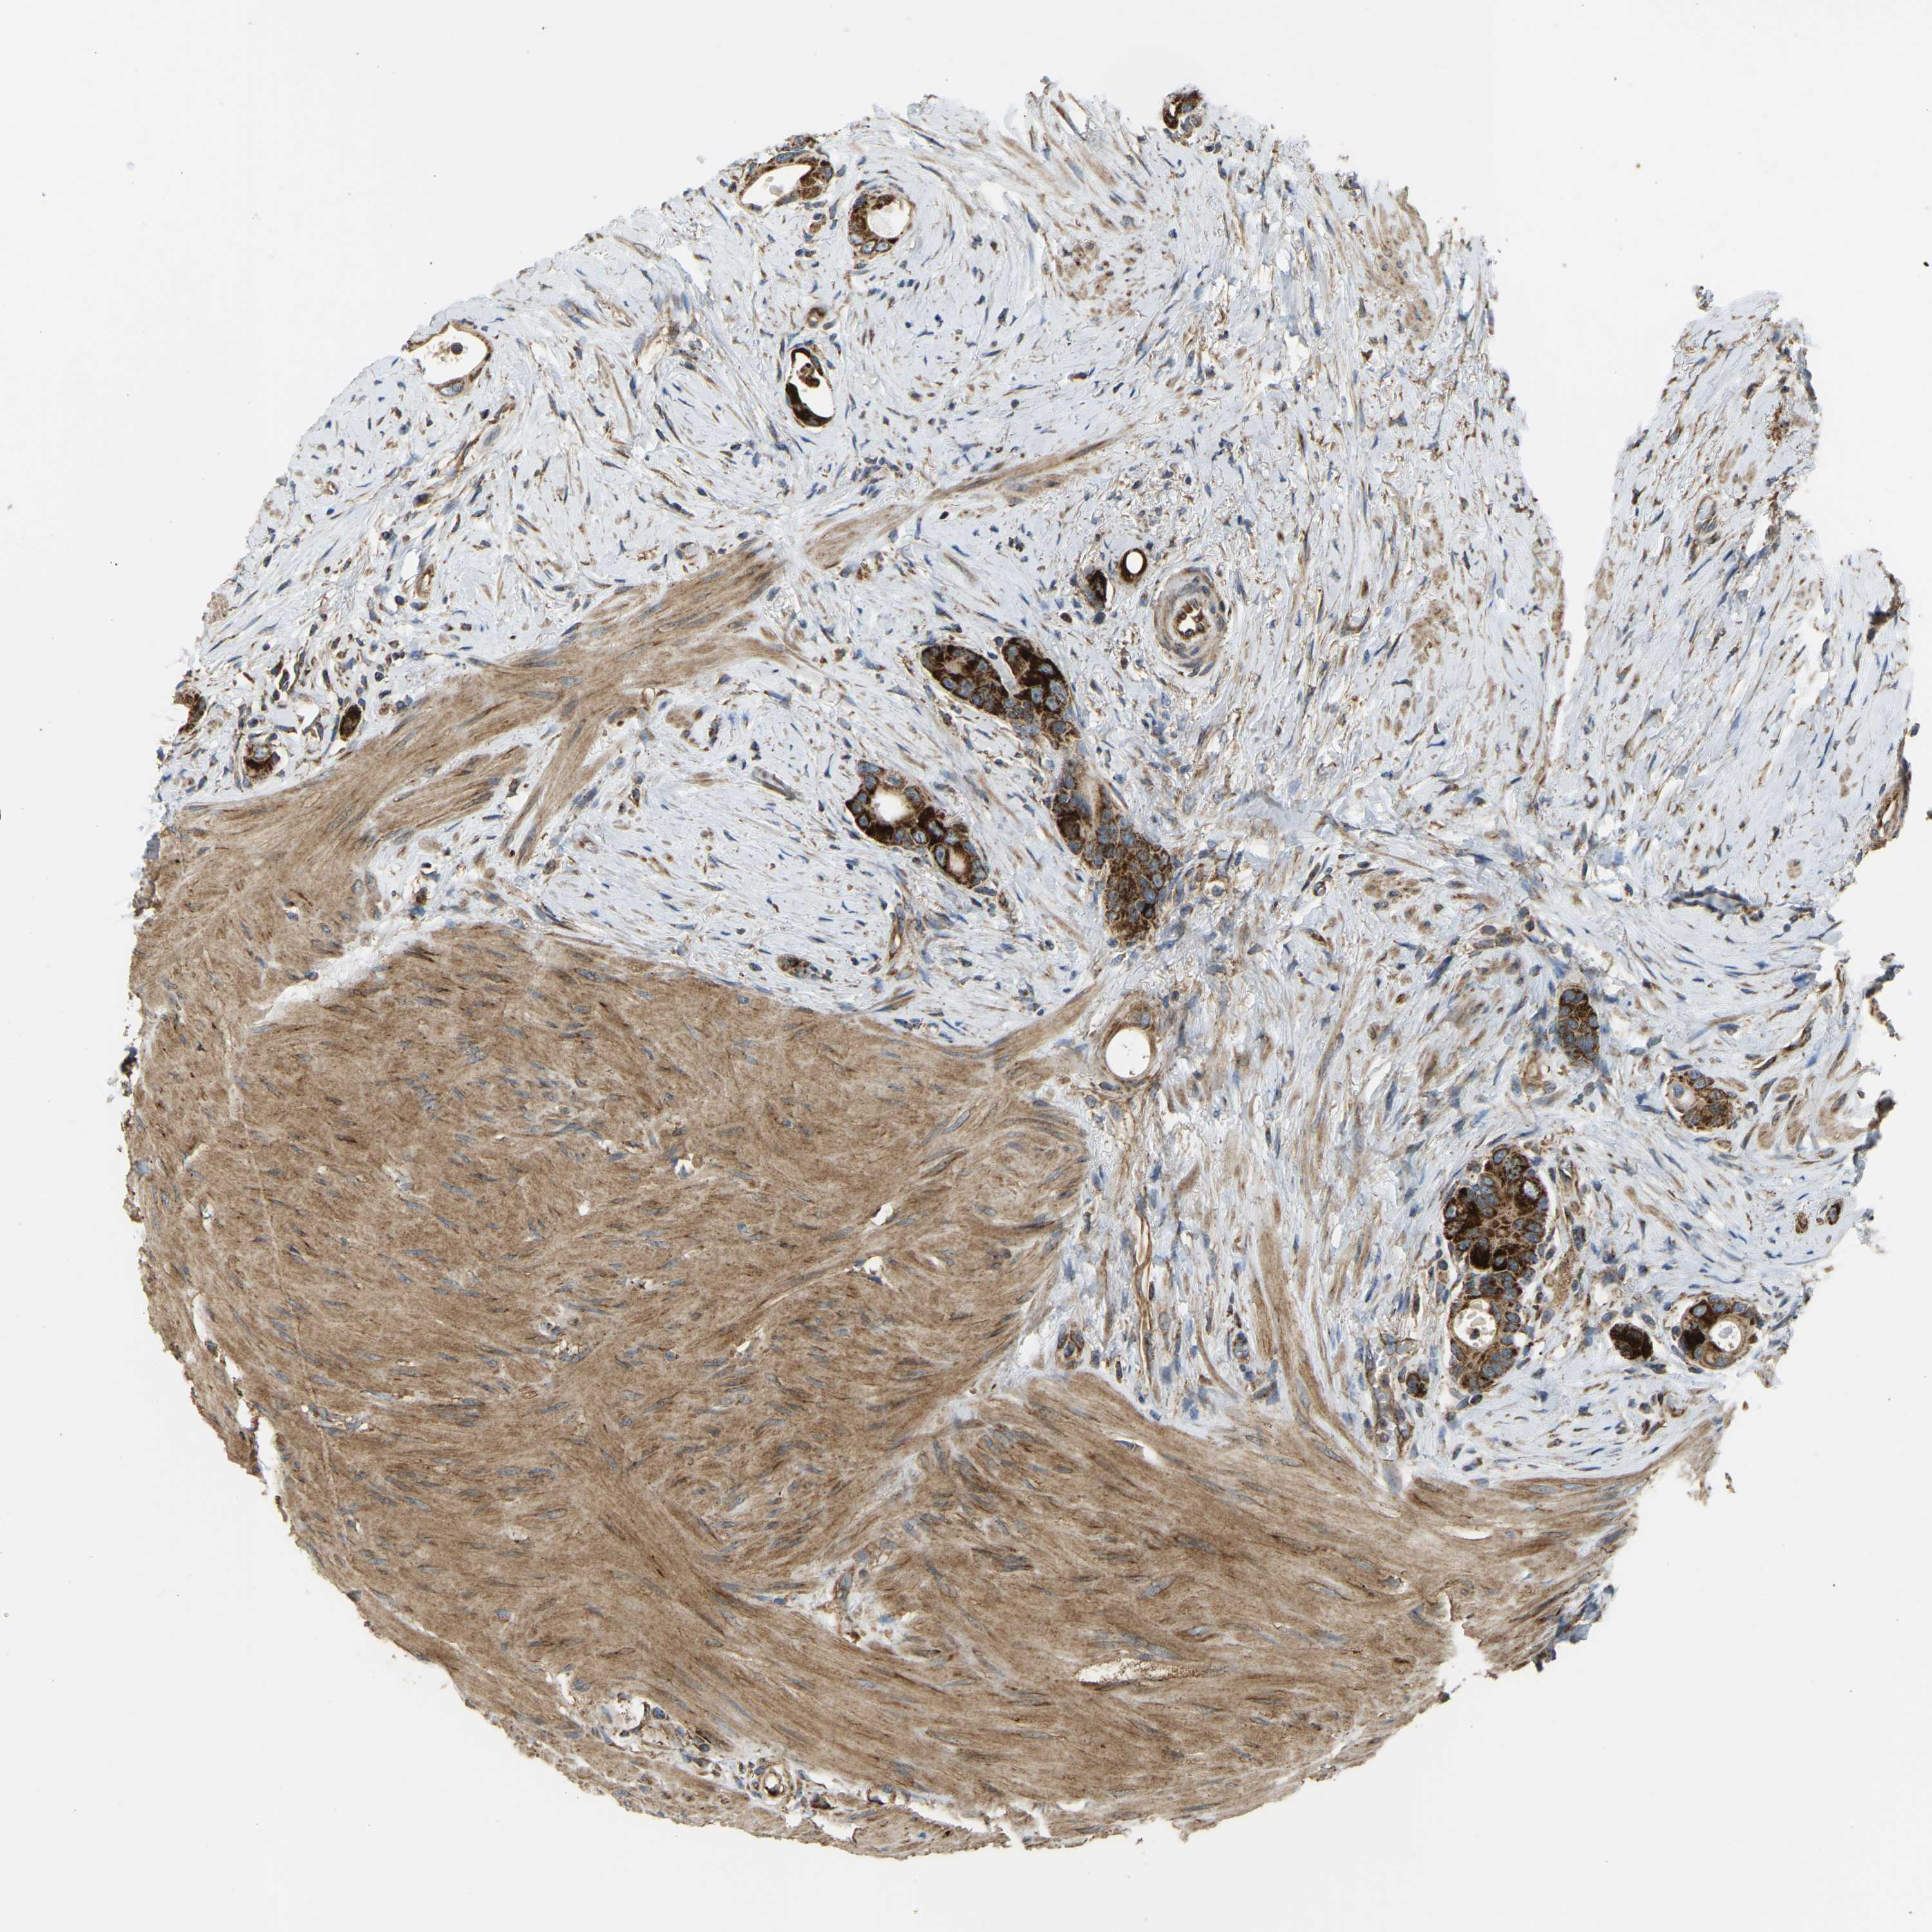

CANCER COLORECTAL CANCER Show tissue menu

Colorectal cancer

Human cancer

Colon adenocarcinoma